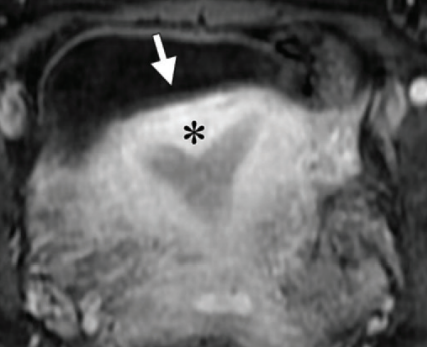

Bicorne VS Septé